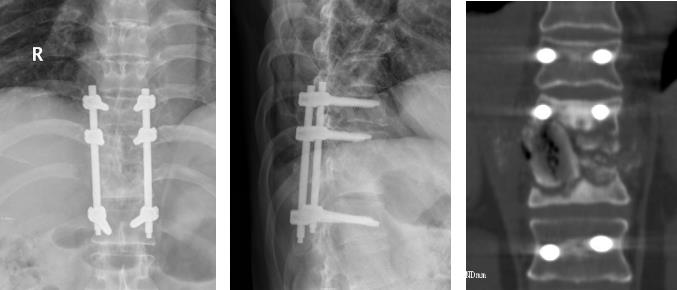

病例 胸10.11椎体结核并双下肢不全瘫,后路胸椎结核病灶清除植骨内固定术。

患者术后下肢肌力、感觉逐渐恢复,术后3个月,下肢肌力恢复至4级。